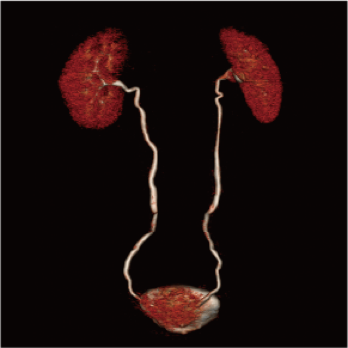

High-power generator delivers high mA output for rapid scanning of complex anatomy and large coverage areas, boosting scan speed while enhancing image signal-to-noise ratio and minimizing artifacts

Wide detector expands single-rotation coverage, shortens exam time, reduces motion artifacts, decreases radiation dose, and saves tube exposure time while effectively lowering operating costs